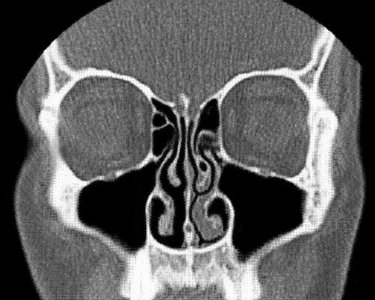

Nasal Cavity – Conchae & Meatuses

Structure and Function

Conchae: Three bony projections (superior, middle, inferior) on the lateral walls of the nasal cavity that increase surface area and help warm, moisten, and filter air.

Meatuses: Passages beneath each concha that direct airflow and drain sinuses.

Paranasal Sinuses

Sinus Anatomy

Frontal Sinus: Located in the frontal bone above the eyes.

Maxillary Sinus: Largest sinus, located in the maxilla (cheek area).

Sphenoid Sinus: Located in the sphenoid bone, deep within the skull.

Nasal Septum: The partition separating the two nasal cavities.